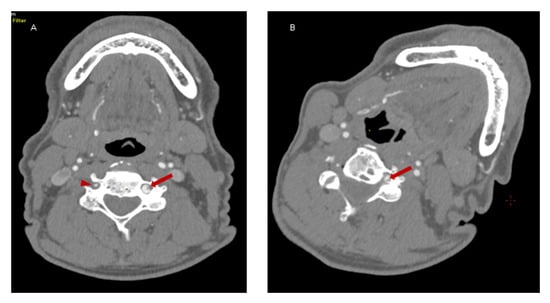

Because of the suspected dynamic stenosis, a dynamic CT angiography (D-CTA) of the carotid, vertebral and cerebral arteries was performed. Firstly, the imaging was conducted with the patient’s head in the neutral position. It revealed atheromatous plaques in both carotid bulbs (slightly calcified; maximum thickness: 2.8 mm) with no hemodynamically significant stenosis, grade 2 of kinking of R-ICA and a tortuosity of L-ICA. Furthermore, hypoplasia of R-VA was demonstrated (widths: R-VA 1.9 mm; L-VA 3.6 mm). L-VA had a tortuous course and it formed a loop at the level of the C4 vertebrae. There was no L-VA stenosis in this position (Figure 2A). Subsequently, D-CTA was acquired during left-side rotation of the head. In this examination the lumen of L-VA was narrowed up to 2 × 3.2 mm, causing 60% stenosis according to the NASCET criteria (Figure 2B) [7]. 3D reconstructions of this pathology were also obtained (Figure 3A,B). It was also observed that basilar artery (BA) was formed exclusively by L-VA. No abnormalities of other cerebral arteries were observed.

Figure 3. 3D reconstruction in the neutral head position and left-side head rotation. Panel (A): Coronal 3D reconstruction of the vertebral arteries in the neutral position of the head demonstrates L-VA loop in V2 segment at C4 level (yellow arrow) and R-VA hypoplasia (yellow arrowhead). No L-VA stenosis in this position. BA is formed exclusively by L-VA (red arrow). Panel (B): Coronal 3D reconstruction of the vertebral arteries in left-side head rotation demonstrates the narrowing of L-VA lumen (up to 2 mm × 3.2 mm) that causes a dynamic 60% L-VA stenosis in the loop at C4 level (yellow arrow).